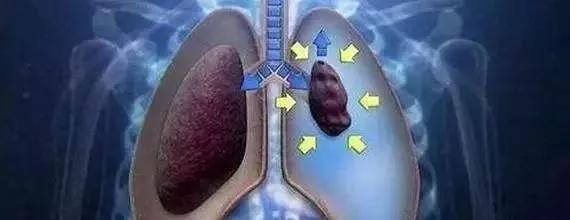

自发性气胸,依书直说,是指因肺部疾病使肺组织和脏层胸膜破裂,或靠近肺表面的肺大疱、细微气肿疱自行破裂,使肺和支气管内空气漏到胸腔,压缩肺组织。通俗地讲,肺就像是轮胎,轮胎爆胎,漏气了。根据发病原因和临床表现可以分为原发性和继发性两种,原发性自发性气胸是指患者并没有相关的肺病而自发形成的气胸,目前普遍认为,其主要由于肺大泡引起,这种类型以小年轻为多见。其中继发性自发性气胸由肺病疾病引起,大多数发生于45岁以上男性。

这就是传说中的肺大泡,非常容易破裂,它在CT上长这个样子……